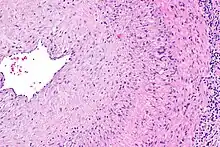

The gold standard for diagnosing temporal arteritis is biopsy, which involves removing a small part of the vessel under local anesthesia and examining it microscopically for giant cells infiltrating the tissue.[19] However, a negative result does not definitively rule out the diagnosis; since the blood vessels are involved in a patchy pattern, there may be unaffected areas on the vessel and the biopsy might have been taken from these parts. Unilateral biopsy of a 1.5–3 cm length is 85-90% sensitive (1 cm is the minimum).[20] A characterised as intimal hyperplasia and medial granulomatous inflammation with elastic lamina fragmentation with a CD 4+ predominant T cell infiltrate, currently biopsy is only considered confirmatory for the clinical diagnosis, or one of the diagnostic criteria.

- Histological features of temporal arteritis

- Histopathology of giant cell vasculitis in a cerebral artery. Elastica-stain.